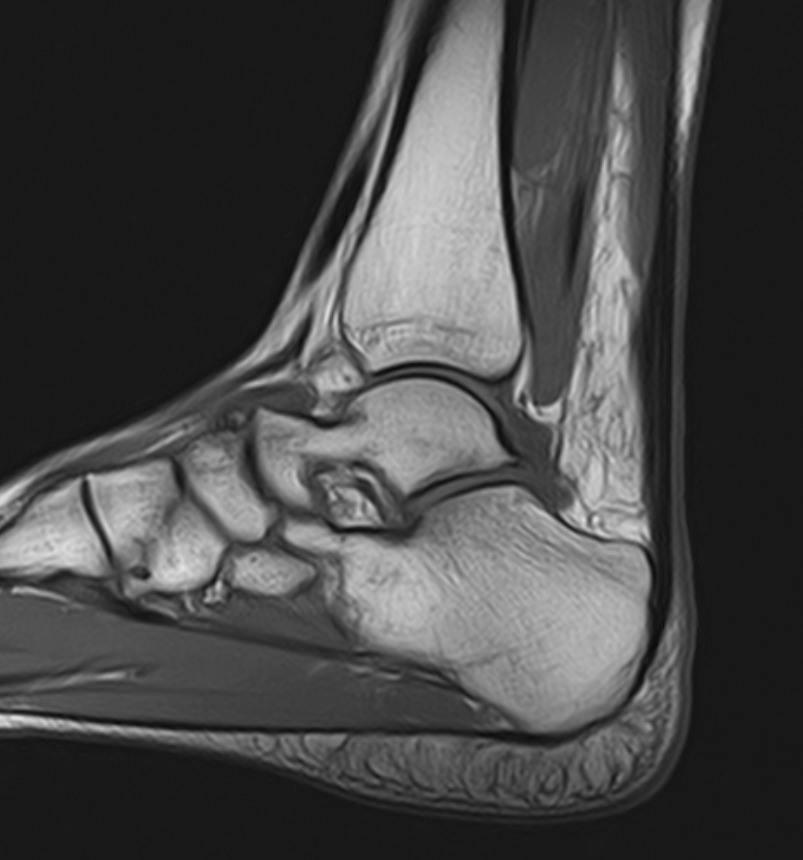

Наиболее точным и достоверным методом диагностики заболеваний голеностопного сустава является магнитно-резонансная томография. МРТ дает максимально полную информацию о состоянии всех анатомических структур сустава, включая костную ткань, сухожилия, связочный аппарат, нервные волокна и прилежащие мягкие ткани. Кроме высокой информативности метод МРТ является достаточно быстрой и безболезненной процедурой, при этом отличается безопасностью (нет рентгеновского облучения) и доступной ценой.

В нашей клинике можно пройти МРТ голеностопного сустава на современном высокопольном томографе экспертного класса TOSHIBA VANTAGE TITAN 1,5 Тесла, обладающего превосходной разрешающей способностью и создающего изображения с высокой детализацией и точностью.

Что покажет МРТ голеностопного сустава?

Снимки МРТ голеностопа показывают широкий спектр суставных заболеваний, включая:

• абсцесс и артрит, ахиллесов тендинит;

• трещины костей сустава и переломы;

• все разновидности костных инфекций;

• надрывы, растяжения и травмы сухожилий и хрящей;

• повреждение мышц голеностопа, остеонекроз (аваскулярный некроз);

• разрыв подошвенной фасции, дисфункции сухожилий;

• разрыв ахиллова сухожилия в области лодыжки;

• злокачественные и доброкачественные новообразования костных или мягких тканей;

• ущемление нервов, деформации, подагру, артроз;

• нарушение кровообращения в сосудистом русле сустава.